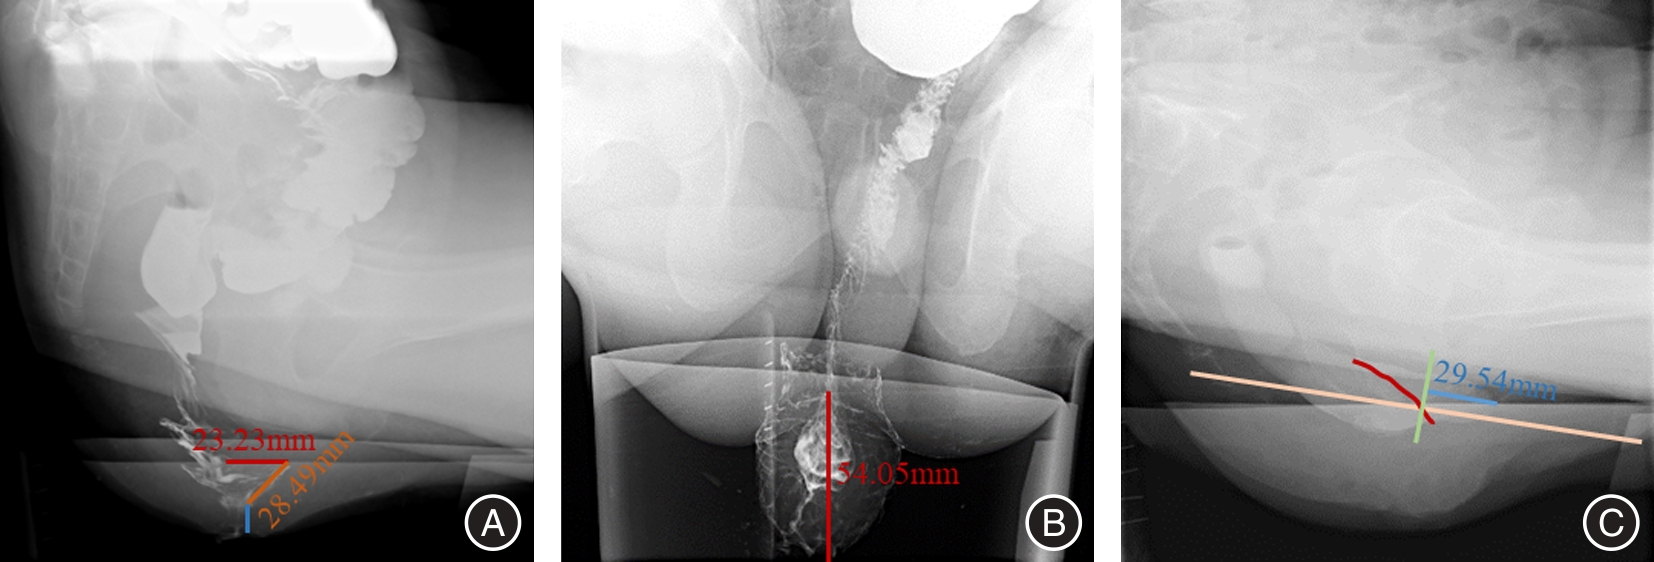

目的 回顾性总结分析孤立性直肠溃疡综合征(SRUS)患者的X线排粪造影(XRD)和MR排粪造影(MRD)的影像学表现,为临床诊疗提供重要信息。 方法 19例经临床、病理和肠镜检查证实的SRUS患者纳入本研究,15例行XRD,7例行MRD,3例患者同时进行了XRD和MRD检查。收集所有患者的数据并进行盆底功能测量。 结果 在XRD结果中,3例(20%)表现直肠内套叠,8例(53.3%)直肠外脱垂,2例(13.3%)中度直肠前突。另外耻骨直肠肌肥厚患者有2例,膀胱脱垂和子宫脱垂患者各有1例。在MRD结果中,3例(42.9%)表现直肠黏膜脱垂(部分性脱垂),4例(57.1%)直肠前突患者中,3例(均为女性)为中度直肠前突,1例为轻度直肠前突。3例患者同时观察到相关的前、中腔室器官下降,2例耻骨直肠肌肥厚,没有患者表现乙状结肠疝。 结论 排粪造影可以评估SRUS患者的直肠外脱垂、直肠前突、直肠黏膜脱垂、直肠内套叠等盆底结构及功能异常,对SRUS患者的治疗具有指导意义。

Objective The imaging findings of X?ray defecography (XRD) and magnetic resonance defecography (MRD) of patients with Solitary Rectal Ulcer syndrome (SRUS) were retrospectively analyzed to provide important information for clinical diagnosis and treatment. Methods 19 patients with SRUS confirmed by clinical, pathological and colonoscopy were included in this study. Among them, 15 patients underwent XRD and 7 patients underwent MRD, and 3 patients underwent both XRD and MRD. Data of all enrolled patients were collected and pelvic floor function was measured. Results In the results of XRD, 3 patients (20%) showed rectal intussusception. 8 patients (53.3%) showed external rectal prolapse and 2 patients (13.3%) showed moderate rectocele. In addition, there were 2 patients of puborectal muscle hypertrophy, and 1 patient of bladder prolapse and uterine prolapse, respectively. For MRD, 3 patients (42.9%) showed rectal mucosal prolapse (partial prolapse). At 4 patients (57.1%) with rectocele, 3 patients (all female) had moderate rectocele, 1 patient had mild rectocele. 3 patients were also observed related anterior and middle compartment organ descent. 2 patients of pubulorectal muscle hypertrophy, no sigmoidocoele. Conclusion Defecography can evaluate the structural and functional abnormalities of pelvic floor in SRUS patients, such as external rectal prolapse, rectal protrusion, rectal mucosal prolapse, and rectal intussusception, which has guiding significance for the treatment of SRUS patients。